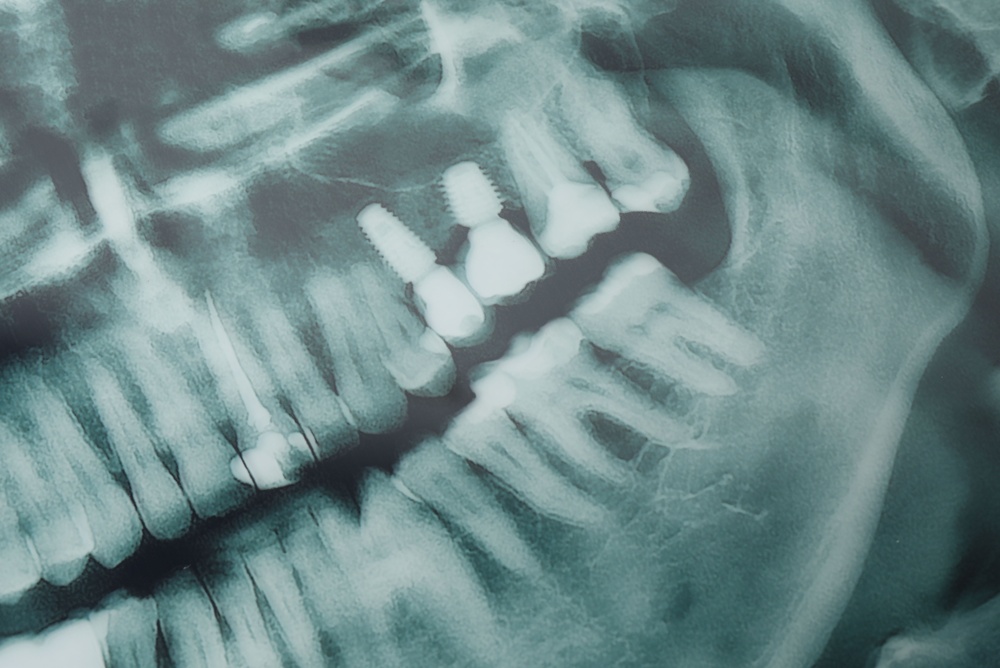

A dental implant abutment is the middle piece of a three-part implant restoration. The three parts are the implant (the titanium or ceramic fixture placed in the bone), the dental implant abutment (the connector), and the crown or prosthesis (the visible tooth). The abutment screws or fits onto the implant and provides the foundation for the crown. Without a properly fitted abutment, the prosthesis won’t sit correctly or function like a natural tooth.

The abutment transfers your bite forces from the crown to the implant and then into the jawbone. It shapes the emergence profile—the way the crown meets the gum—so the final tooth looks natural. A good abutment also supports the surrounding soft tissue and creates a tight seal to reduce bacterial entry around the implant. Proper fit and material choice help prevent micro-movement and reduce the risk of complications like loosening or gum inflammation.